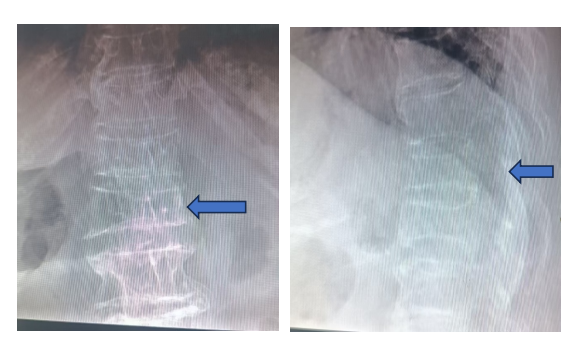

术前X光片显示:T12压缩骨折,椎体压缩,变扁

术后X光片显示:椎体高度恢复

麻醉完全清醒后即可翻身起床,术后第1天就佩带腰围下地行走,疼痛明显缓解,术后第3天就出院了。同时,微创手术还纠正了胸椎T12骨折导致的椎体高度丢失,防止了老人家驼背的加重。